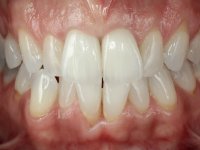

A paciente não gostava das coroas que tinha colocadas nos incisivos centrais. Não gostava que se visse o “escuro das raízes”. Não gostava também da tonalidade dos outros dentes, estavam “muito amarelos”.

Paciente do sexo feminino com 41 anos de idade, não fumadora. Apresentava duas coroas sobre espigões falsos cotos fundidos nos dentes 1.1 e 2.1. As coroas apresentavam-se com infiltrações cervicais com exposição da superfície radicular. A papila gengival mediana, apresentava-se ligeiramente retraída. O espaço mesio-distal correspondente às duas coroas mostrava-se alto e estreito. Apresentava um ligeiro apinhamento dos incisivos inferiores, bem como uma pequena retração gengival. No sorriso era bem visível a zona cervical das coroas, mostrando um aspeto acinzentado correspondendo ao escurecimento radicular. No exame imagiológico verificou-se que o tratamento endodôntico não estava tecnicamente satisfatório, mas assintomático à quase 10 anos.